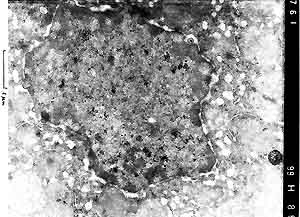

- Case 22-4. Liver (per contributor) TEM. Scattered

within the nucleus are multiple, 100nm diameter, viral particles

(central nucleoid surrounded by a capsid = [nucleocapsid]). Occasional

virions, 150-200nm in diameter, are acquiring an envelope from

the inner nuclear membrane.

- Electron microscopy of liver tissue revealed numerous viral

particles with nucleocapsid and characteristic symmetry within

nuclei of hepatocytes in the periphery of the necrotic foci.

The viral particles measured approximately 100 nm in diameter.

Occasionally virions, 150 to 200 nm in diameter, obtaining an

envelope from the inner membrane of the nucleus could be seen.

Histologic and electron microscopic findings are consistent with

alphaherpesvirus infection (Herpes simplex or Herpes